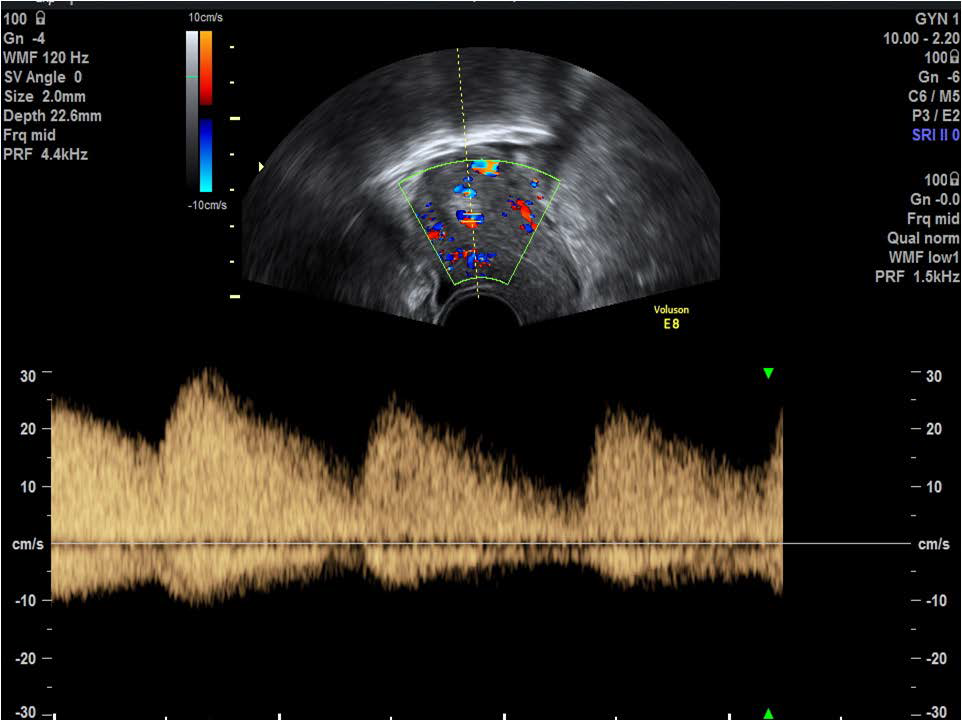

Figure 6: Application of colour Doppler demonstrates trophoblastic blood flow to the region of the echogenic mass, aiding diagnosis of retained products of conception.

figure 6